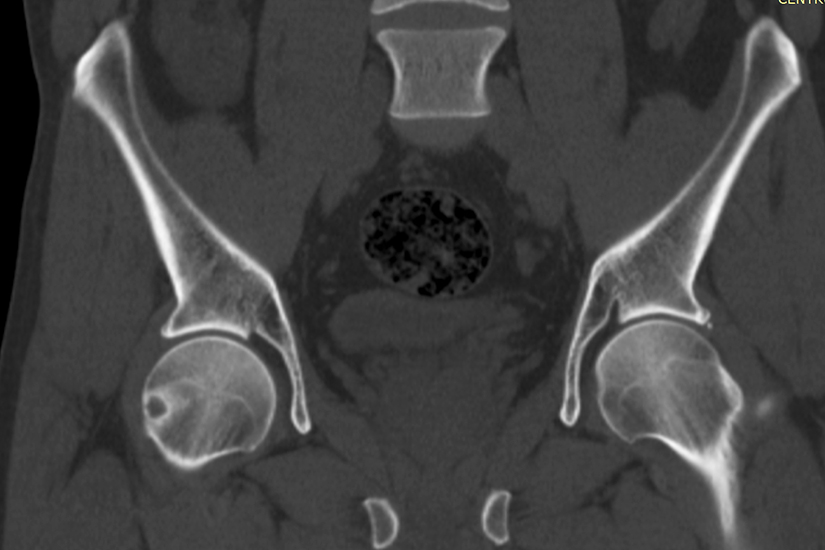

Si in cazul de fata, procesul de diagnosticare a fost unul indelungat. Pacientul, in varsta de 35 de ani, a aflat ca are o tumora osoasa benigna la 2 ani distanta de la realizarea primei investigatii. “In 2018 am facut un RMN la Suceava, care arata ca am doua chisturi osoase la nivelul femurului drept. Timpul a trecut, iar anul acesta (2020, n. red.) am facut un nou RMN pentru ca aveam dureri permanente si nu stiam ce am. Am facut si investigatii pentru ficat, am fost si la neurochirurg deoarece credeam ca este ceva la coloana. Medicul neurochirurg mi-a recomandat sa merg la un chirurg ortoped si mi l-a recomandat pe domnul doctor Voicu. Am mers la dansul si am facut un CT si asa am aflat de aceasta tumora”, ne-a marturisit pacientul.

Osteomul osteoid este o tumoare osoasa benigna extrem de dureroasa observata frecvent la persoanele tinere. A fost descoperita prin anii 1930 si are o incidenta raportata de 2%-3% in randul tuturor tumorilor primare osoase. Desi este o leziune mica si benigna, poate cauza dureri extreme, afectand abilitatea pacientului de a-si duce la bun sfarsit activitatile zilnice obisnuite.